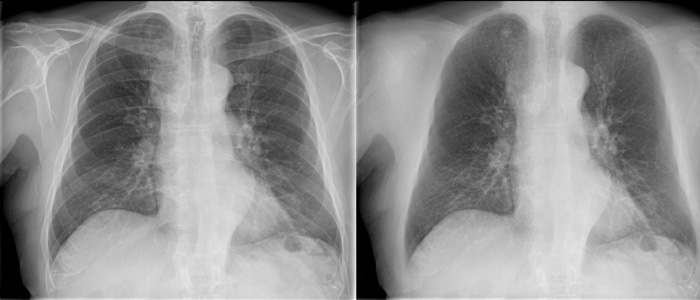

Bone Suppression

Bone Suppression**

Innovative image enhancement technology designed to increase the clarity of adult erect chest radiographs by suppressing bones on digital images.

• More confident image interpretation

• Enables detection of 1 in 6 nodules previously missed

• Fully integrated into the Eleva workflow

• Images automatically added to patient files